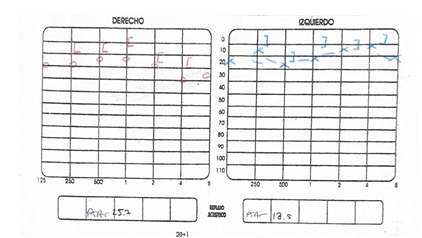

A la exploración física se palpa tumoración en nivel II de cuello derecho de aproximadamente 6 cm x 3 cm, de bordes regulares, de consistencia dura, no móvil, no dolorosa a la palpación, fija a planos profundos, y en cavidad oral se observa amígdala derecha grado IV, de apariencia lobulada, hiperémica, firme, cubierta por exudado blanquecino, no ulcerada, no sangrante, dolorosa a la palpación, que desplaza medialmente el paladar blando. (Figura 1).

Se realiza tomografía computarizada contrastada de cráneo y cuello; en la cual se observa a nivel de amígdala palatina derecha, una lesión isodensa a tejidos blandos de bordes regulares, que disminuye la luz de la vía aérea y desplaza al espacio parafaríngeo ipsilateral, que no realza al paso del medio de contraste (Figura 2).

La paciente fue sometida a una biopsia incisional de la lesión, se extrajo un espécimen de 3 x 1.9 cm, a la visión macroscópica de superficie rugosa, de coloración blanca grisácea y de consistencia blanda; dicha muestra se envió al servicio de patología para su estudio, con un resultado de Linfoma No Hodgkin difuso de centro folicular de estirpe de células “B”. (Figura 5). Al igual se realizó inmunohistoquímica la cual reportó CD-3, CD-10, CD-20, BCL-2, BCL-6 Y Ki-67 positivos. (Figura 6 y 7).

El tipo folicular de LNH que se demostró en el presente caso se encuentra con menor frecuencia, y el patrón de crecimiento de los linfocitos pequeños se caracteriza por folículos neoplásicos mal formados, constituidos por centrocitos y centroblastos. Desde el punto de vista inmunohistoquímico, los LNH foliculares revelan expresiones de CD 10. La tinción positiva con anticuerpos frente a la molécula antiapoptótica Bcl-2 y Bcl-6 es bastante común. La sobreexpresión del gen Bcl-2 inhibe la apoptosis en las células afectadas y consecuentemente resulta en la expansión incontrolable de los tejidos linfoides.10 Los LNH foliculares responden mal a la radioterapia, quimioterapia o combinación de ambas. Además, en aproximadamente un 40% de los casos puede observarse la transformación de la enfermedad en un subtipo de linfoma más agresivo, el LCDGB. La tasa de supervivencia global a los 5 años depende principalmente del estadío de la neoplasia en el momento del diagnóstico y varía entre un 50 a un 80% para los LNHs de la región maxilofacial. Por todo ello el diagnóstico temprano resulta imperativo.